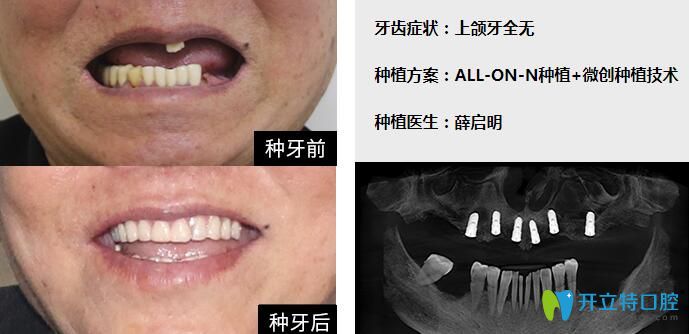

上半口仅剩1颗松动牙齿,而且没有保留价值;种植方案:拔除残牙后,采用

图片尺寸689x334